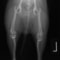

■ 症例20 ポメラニアン 8ヶ月 1.8kg

左右膝蓋骨脱臼 グレードⅢ

2ヶ月前から間欠的跛行が認められ、両膝の膝蓋骨脱臼整復術を行った。

手技は縫工筋及び内側広筋の解放、脛骨粗面の外側転位、滑車ブロック形造溝術、内外側関節包の縫縮を選択し実施した。

右側の膝蓋骨脱臼は上記手技で整復されたものの、左側はそれのみでは膝蓋骨が浮く様子が認められた。その為、PDS縫合糸にて膝蓋靱帯を1糸のみ縫合し、靱帯の縫縮を行った。

膝蓋骨脱臼は膝関節における膝蓋骨の内外側の脱臼と定義されるが、時として単純な内外の脱臼ではなく、膝蓋骨が大きく前方に浮き上がるように脱臼する場合がある。特にトイプードルやポメラニアンといった犬種に多く認められる。

内側脱臼に加えて前方への浮き上がりを矯正する為に、従来より脛骨粗面転移により膝蓋靭帯を外方と下方に引っ張り、固定する方法を選択する。膝蓋骨の前方への浮き上がりが軽度の場合は、従来法ではなく関節包の縫縮で対応していた。しかし、一部の症例で膝蓋骨の動きが悪くなり伸展機構が円滑に機能せずロボット様歩行になるケースがあった。

その為、膝蓋靭帯自体を縫縮する方法を採用した。この方法により、膝関節の伸展機構を妨げず膝蓋骨の軽度の浮きを矯正することが可能となった。

本症例の経過は良好である